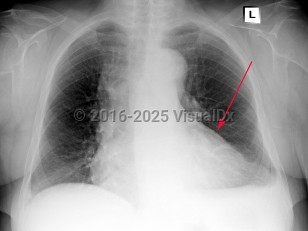

Tension pneumothorax